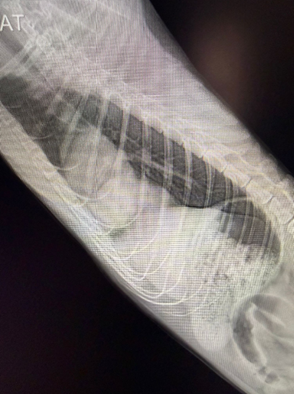

圖二| 另一角度X光可見胸腔內異常軟組織密度,支持肝臟移位進入胸腔的判斷。